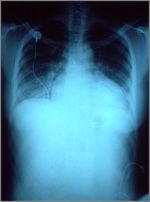

The enlarged cardiac silhouette on this AP x-ray is due to congestive heart failure. Fluid has accumulated in the lungs in what is known as pulmonary congestion.